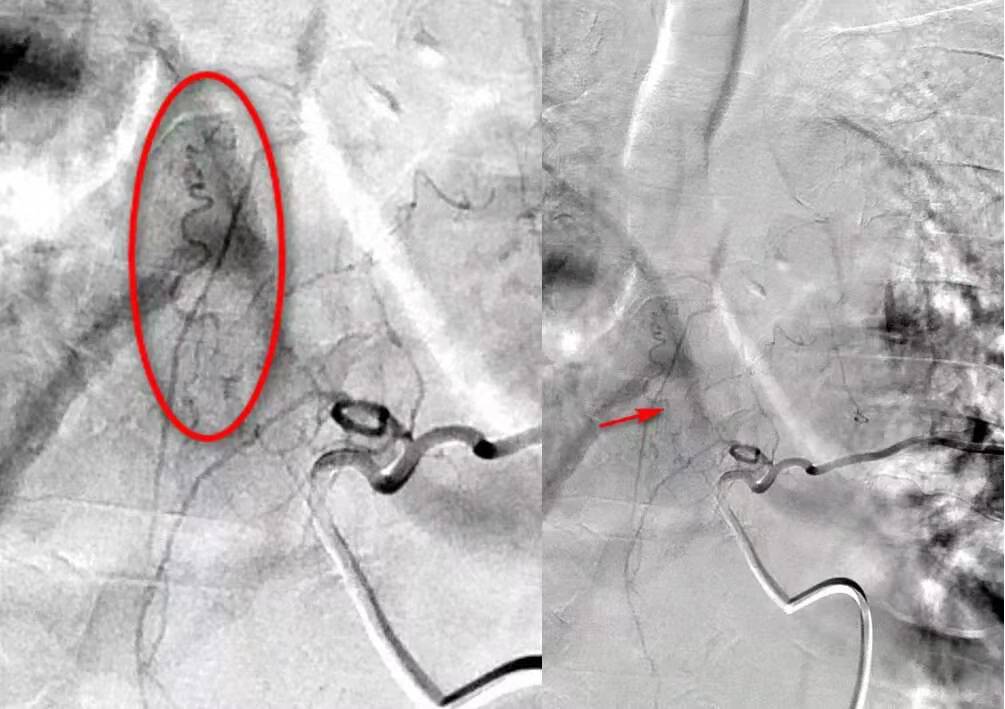

基本情况:王某,男,61岁。入院时间:2019年8月9日。主诉:双下肢麻木无力半年。

现病史:患者半年前无诱因出现双下肢麻木、无力,逐渐向上延伸,左下肢无力显著,伴行走不稳,随后出现大小便困难。8月3日给予糖皮质激素治疗后,双下肢麻木无力加重。